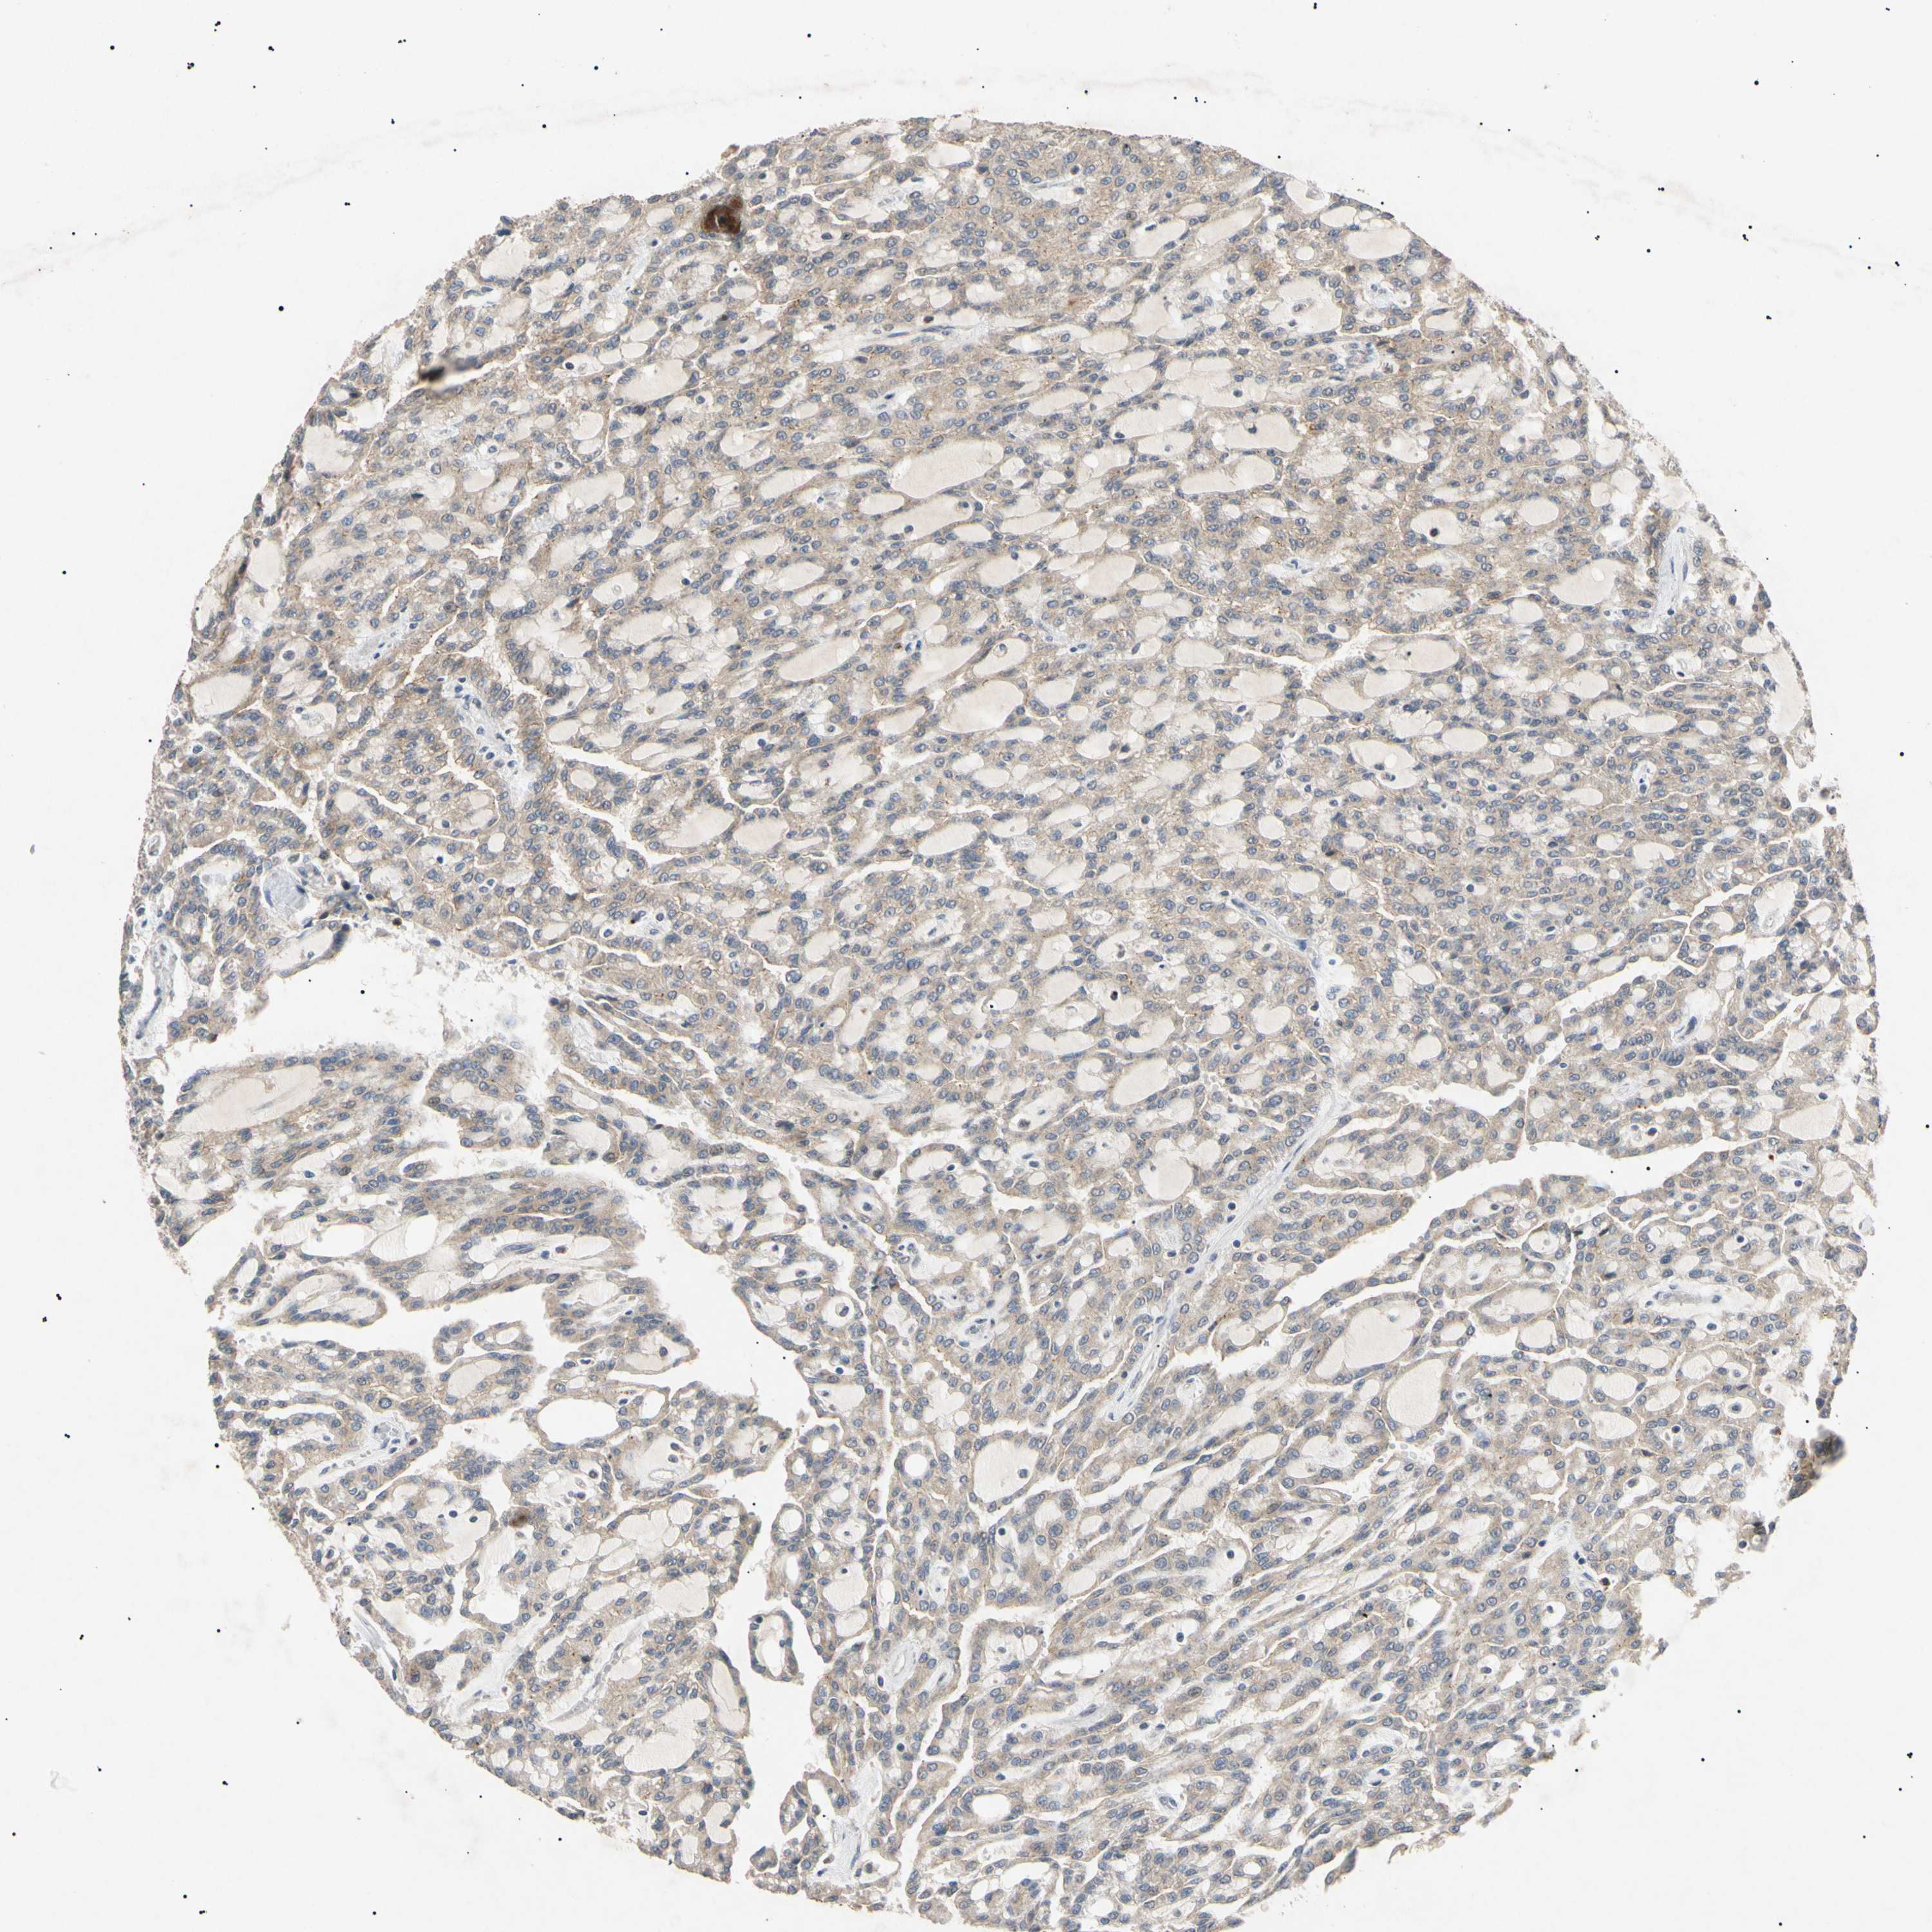

KIDNEY RENAL CLEAR CELL CARCINOMA (VALIDATION) - Interactive survival scatter ploti

The Survival Scatter plot shows the clinical status (i.e. dead or alive) for all individuals in the patient cohort, based on the same data that underlies the corresponding Kaplan-Meier plots. Patients that are alive at last time for follow-up are shown in blue and patients who have died during the study are shown in red.

The x-axis shows the expression levels (FPKM) of the investigated gene in the tumor tissue at the time of diagnosis. The y-axis shows the follow-up time after diagnosis (years). Both axes are complimented with kernel density curves demonstrating the data density over the axes. The top density plot shows the expression levels (FPKM) distribution among dead (red) and alive patients (blue). The right density plot shows the data density of the survived years of dead patients with high and low expression levels respectively, stratified using the cutoff indicated by the vertical dashed line through the Survival Scatter plot. This cutoff is automatically defined based on the FPKM cutoff that minimizes the p-score. The cutoff can be changed by dragging the vertical line or by entering a cutoff value in the square labeled "Current cut-off".

Under the Survival Scatter plot the p-score landscape (black curve; left axis) is shown together with dead median separation (red curve; right axis). Dead median separation is the difference in median mRNA expression between patients who have died with high and low expression, respectively. It is calculated as follows: median FPKM expression of dead patients with high expression - median FPKM expression of dead patients with low expression. This is intended to aid the user in visually exploring custom cutoffs and the associated p-scores and dead median separation.

Individual patient data is displayed and can be filtered by clicking on one or more of the category buttons on the top of the page. Categories describing expression level and patient information include: high, low, alive, dead, female, male and tumor stages. The scale of the x-axis can be toggled between linear and log-scale by clicking on the "x log" button. Mouse-over function shows TCGA ID, patient information and mRNA expression (FPKM) for each patient.

& Survival analysisi

Kaplan-Meier plots summarize results from analysis of correlation between mRNA expression level and patient survival. Patients were divided based on level of expression into one of the two groups "low" (under cut off) or "high" (over cut off). X-axis shows time for survival (years) and y-axis shows the probability of survival, where 1.0 corresponds to 100 percent.

TUBB4A is not prognostic in Kidney Renal Clear Cell Carcinoma (validation)

Best expression cut offi

Based on the FPKM value of each gene, patients were classified into two groups and association between prognosis (survival) and gene expression (FPKM) was examined. The best expression cut-off refers the FPKM value that yields maximal difference with regard to survival between the two groups at the lowest log-rank P-value. Best expression cut-off was selected based on survival analysis .

When clicking on this number, the vertical dashed line indicating cut-off, the interactive survival plot, and the Kaplan-Meier curve will be adjusted to show results based on the best expression cut-off.

: 1.37

TCGA RNA samplesi

RNA-seq data is reported as average FPKM (number Fragments Per Kilobase of exon per Million reads), generated by the The Cancer Genome Atlas (TCGA) .

Normal distribution across the dataset is visualized with box plots, shown as median and 25th and 75th percentiles. Points are displayed as outliers if they are above or below 1.5 times the interquartile range. FPKM values of the individual samples are presented next to the box plot.

Average pTPM 5.7

Number of samples 100